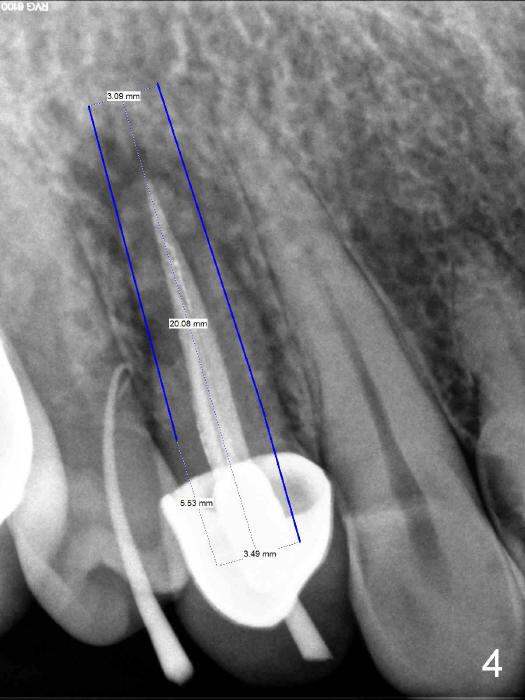

The socket of an upper first premolar is oval (Fig.5), whereas majority of implants are rounded. It is always a mismatch. An implant that matches the shape of the socket most closely is "D" Plateau Implant (Fig.5 insert, Fig.6). The D implant that is appropriate for your case is called D2. It is 20 mm long (Fig.4). On cross section is 5.5 mm wide and 3.5 mm tall at crest (widest portion, Fig.6 insert). The D implant is tapped in. Immediate provisional can be installed. Are you interested in the D implant? Crown forms are needed for the provisional.